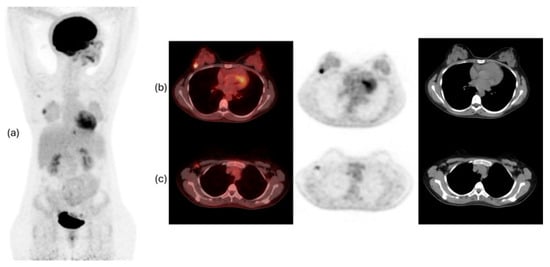

- Richter, A.; Knorr, K.; Schlapschy, M.; Robu, S.; Morath, V.; Mendler, C.; Yen, H.-Y.; Steiger, K.; Kiechle, M.; Weber, W.; et al. First in-human medical imaging with a PASylated (89)Zr-labeled anti-HER2 Fab-fragment in a patient with metastatic breast cancer. Nucl. Med. Mol. Imaging 2020, 54, 114–119. [Google Scholar] [CrossRef] [PubMed]